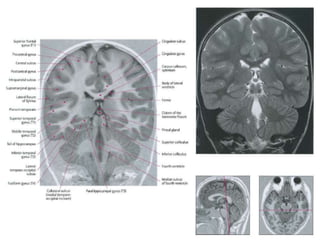

Axial oblique 0.8-mm-thick SSFP MR image

shows the nerve (small arrows) where it

emerges from the interpeduncular cistern

(large arrow), which lies medial to the

cerebellar peduncle (p)

Coronal 0.8-mm-thick SSFP MR image shows

the oculomotor nerve (white arrow) in cross

section between the posterior cerebral artery

(white arrowhead) and the superior cerebellar

artery (black arrowhead), which are distal

branches of the basilar artery (black arrow).

Axial oblique 0.8-mm-thickSSFP MR image shows the nerve (small arrows) where it emerges from the interpeduncular cistern (large arrow), which lies medial to the cerebellar peduncle (p) Coronal 0.8-mm-thick SSFP MR image shows the oculomotor nerve (white arrow) in cross section between the posterior cerebral artery (white arrowhead) and the superior cerebellar artery (black arrowhead), which are distal branches of the basilar artery (black arrow).